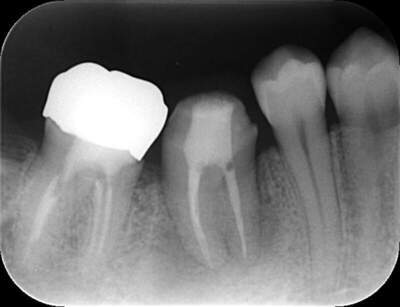

初診時のパノラマレントゲン

説明:

初診時のパノラマレントゲンです。右上の歯が虫歯によって大きく欠けているのがわかります。

3週間後

3週間後のレントゲン写真

移植後3週間経ったら根管治療を行います。根管治療後はレントゲン撮影をし、お薬がしっかり根の先まで充填できているか確認します。この後、土台をたてて、かぶせ物をかぶせて治療終了です。